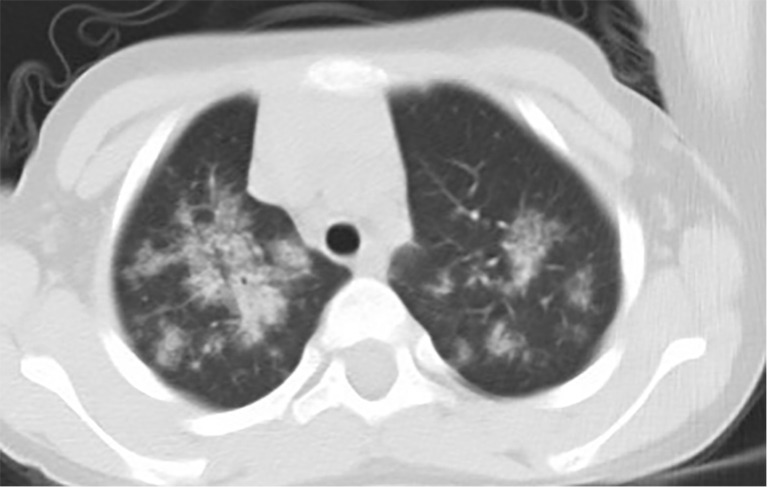

Background: Idiopathic pulmonary hemosiderosis (IPH), a pediatric pulmonary disorder requiring prolonged corticosteroid therapy raises concerns about growth impairment. While corticosteroid-induced stunting is well-documented, its specific impact on the height of IPH patients remains unclear. This study aimed to evaluate the impact of corticosteroid exposure on height outcomes and identify key predictors of growth restriction in children with IPH.

Methods: In this retrospective cohort study, 45 IPH patients [2018-2023] were stratified into normal-stature (n=37) and short-stature (n=8) groups based on anthropometric criteria. Multivariable Cox regression and comparative analyses assessed age at onset, diagnostic delay, corticosteroid duration, nutritional parameters, pulmonary function, and growth hormone (GH) therapy efficacy.

Results: Short-stature patients demonstrated an earlier disease onset (P=0.004) and prolonged diagnostic delay (P=0.002). A younger age at onset independently predicted impaired height growth [hazard ratio (HR) =0.435, 95% confidence interval (CI): 0.206-0.920, P=0.02], while corticosteroid duration showed no association (P=0.45). Secondary analyses identified synergistic effects of anemia (P=0.02), malnutrition (P=0.045), and pulmonary fibrosis (P=0.008). GH therapy significantly improved height velocity (P<0.001) and bone metabolism markers (P<0.05).

Conclusions: Early IPH onset, rather than corticosteroid exposure, drives growth impairment in children. Timely diagnosis, nutritional optimization, and adjunctive GH therapy may mitigate height deficits, underscoring the significance of multidisciplinary management strategies.